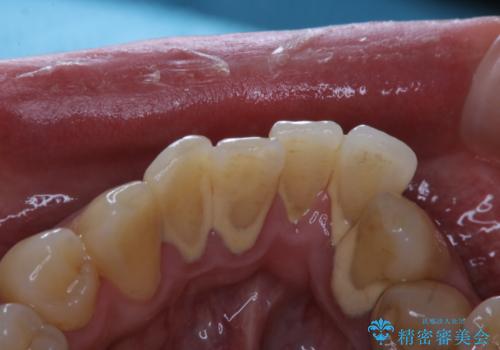

エアフローはお水と強圧の風と細かいパウダーでお掃除していきます。

そのため、ブラシでは届きにくかった歯と歯の間の汚れをより落とすことが可能になります。